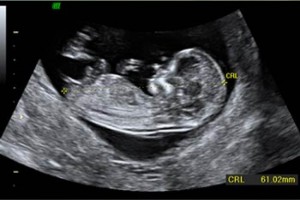

Diplomados en Ultrasonografía